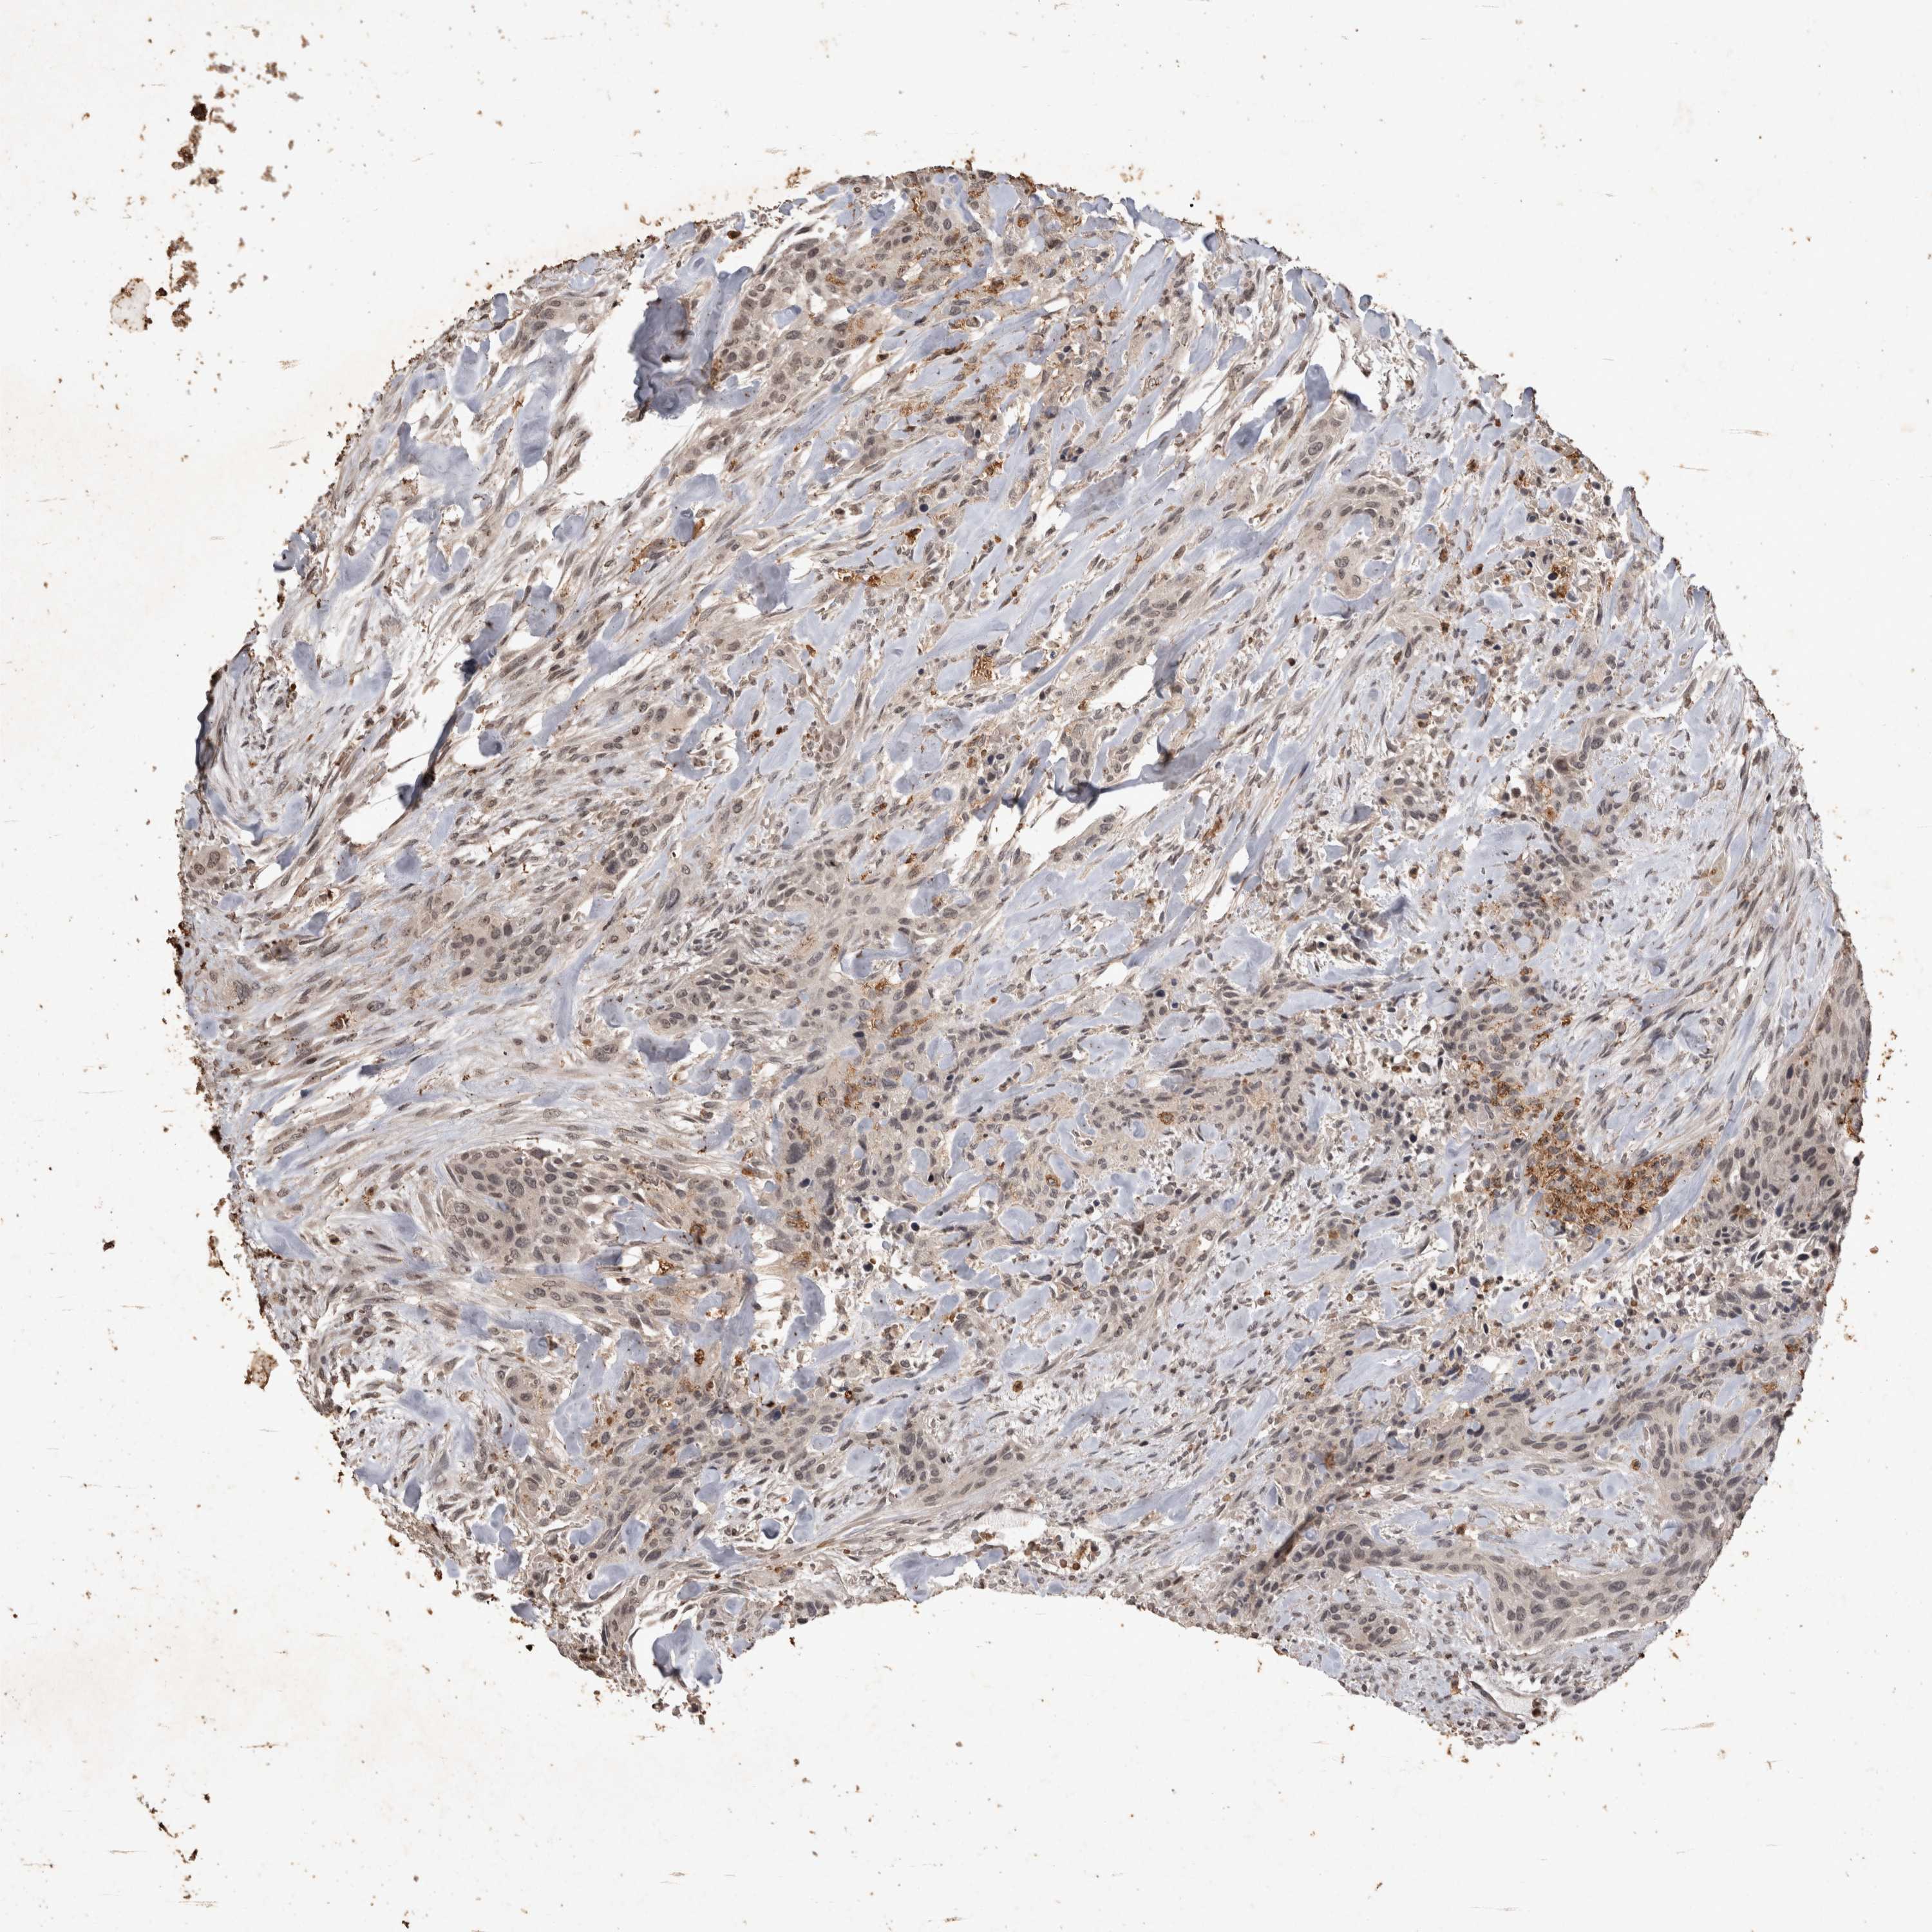

UROTHELIAL CANCER - Protein expressioni

A mouse-over function shows sample information and annotation data. Click on an image to view it in a full screen mode. Samples can be filtered based on level of antibody staining by selecting one or several of the following categories: high, medium, low and not detected. The assay and annotation is described here.

Note that samples used for immunohistochemistry by the Human Protein Atlas do not correspond to samples in the TCGA dataset.

Antibody stainingi

Antibody staining in the annotated cell types in the current human tissue is reported as not detected, low, medium, or high, based on conventional immunohistochemistry profiling in selected tissues. This score is based on the combination of the staining intensity and fraction of stained cells.

Each image is clickable and will lead to virtual microscopy that enables deeper exploration of all samples and also displays staining intensity scores, fraction scores and subcellular localization as well as patient and tissue information for each sample.

Antibody CAB025973

Staining

High

Medium

Low

Not detected

Intensity

Strong

Moderate

Weak

Negative

Quantity

>75%

75%-25%

<25%

None

Location

Nuclear

Cytoplasmic/membranous

Cytoplasmic/membranous,nuclear

Urothelial carcinoma, Low grade

Urothelial carcinoma, High grade